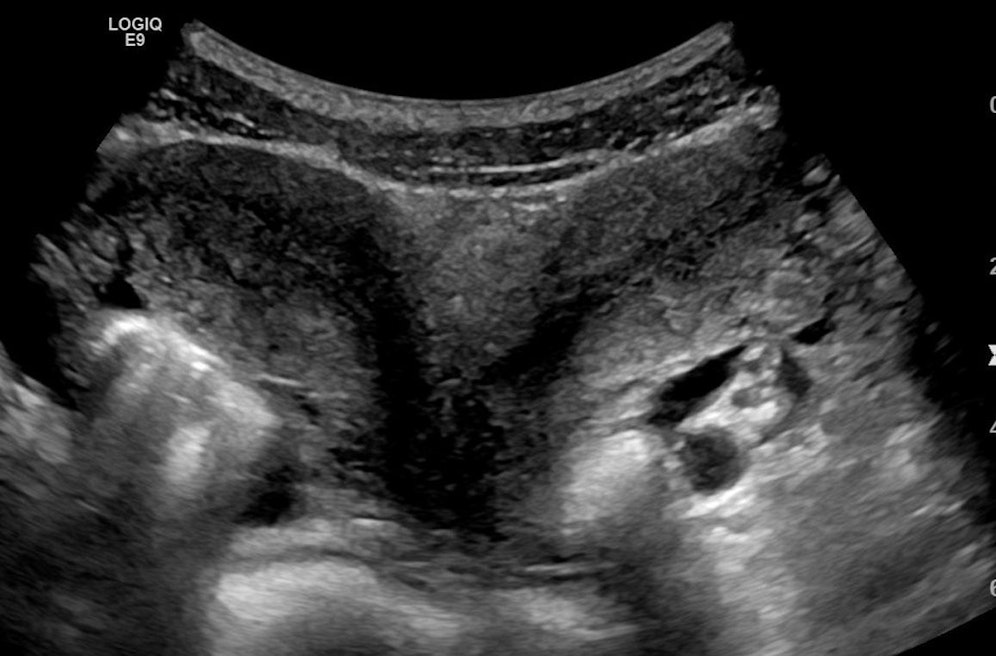

In Israel hat eine Frau mit zwei Gebärmüttern Zwillinge zur Welt gebracht. Es sei jeweils ein Kind in einer Gebärmutter gewachsen, teilte das Ichilov-Krankenhaus in Tel Aviv mit. Die Zwillinge hätten sich also nach der Geburt zum ersten Mal "getroffen". Die Patientin, El Ledovitch, wurde den Angaben zufolge mit einer doppelten Gebärmutter (Uterus didelphys) geboren. Bei dieser Fehlbildung gibt es zwei getrennte Gebärmütter und zwei Gebärmutterhälse. In dem konkreten Fall sei eine Gebärmutter zudem noch in der Mitte geteilt, teilte die Klinik mit.

Eine Zwillingsschwangerschaft sei unter diesen Umständen äußerst selten. Diese besondere Konstellation geschehe mit einer Wahrscheinlichkeit von etwa eins zu einer Million. Die 31-jährige Frau wurde während der Risikoschwangerschaft engmaschig überwacht, die Zwillinge kamen in der 35. Woche per Kaiserschnitt zur Welt.